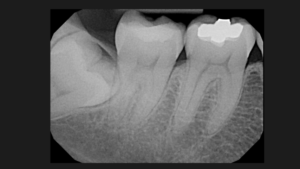

En nuestro Centro radiológico dental, contamos con equipamiento de vanguardia para ofrecerte los mejores resultados en radiografías dentales, radiografías panorámicas dentales, tomografía dental 3D y muchas más. Nuestro equipo de odontólogos está capacitado para brindarte la mejor atención para que tu dentista pueda tomar decisiones informadas sobre tu tratamiento. Además, nuestra radiología digital dental garantiza imágenes de alta calidad y reducción de daños por radiación. Si necesitas una radiografía panorámica dental, no dudes en visitarnos. Contáctanos para conocer nuestros precios y horarios de atención.